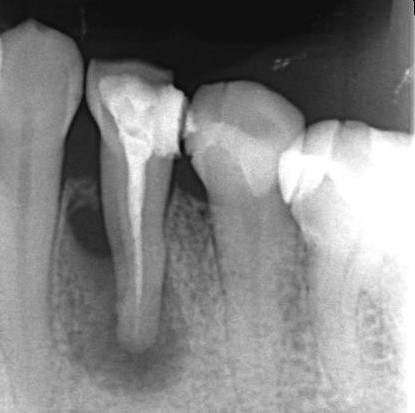

下顎小臼歯部

術前

術後